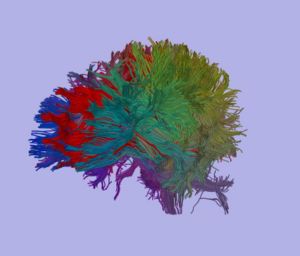

We are using a high resolution 3 Tesla scans, 1.7x1.7x1.7 mm, 51 diffusion directions, 8 baselines (data available to NAMIC investigators). So far we scanned 24 subjects, 12 chronic schizophrenics and 12 matched control subjects. Fiber tractography is performed on the whole brain, and then an automatic clustering method (O’Donnell et al., 2006), is applied. Midsagittal slice is then painted according to anatomical clusters, which results in 5, reliable clusters. Mean FA, mode, trace as well as volume of each clusters are obtained for each subject, and compared between groups.